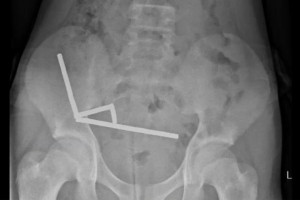

Κόσμος 25.10.25 | 13:45Γιατροί αφαίρεσαν δεκάδες μαγνήτες από τα έντερα 13χρονου Μέχρι και 100 ισχυρούς μαγνήτες που είχε αγοράσει από το Ίντερνετ κατάπιε 13χρονος από τη Νέα...